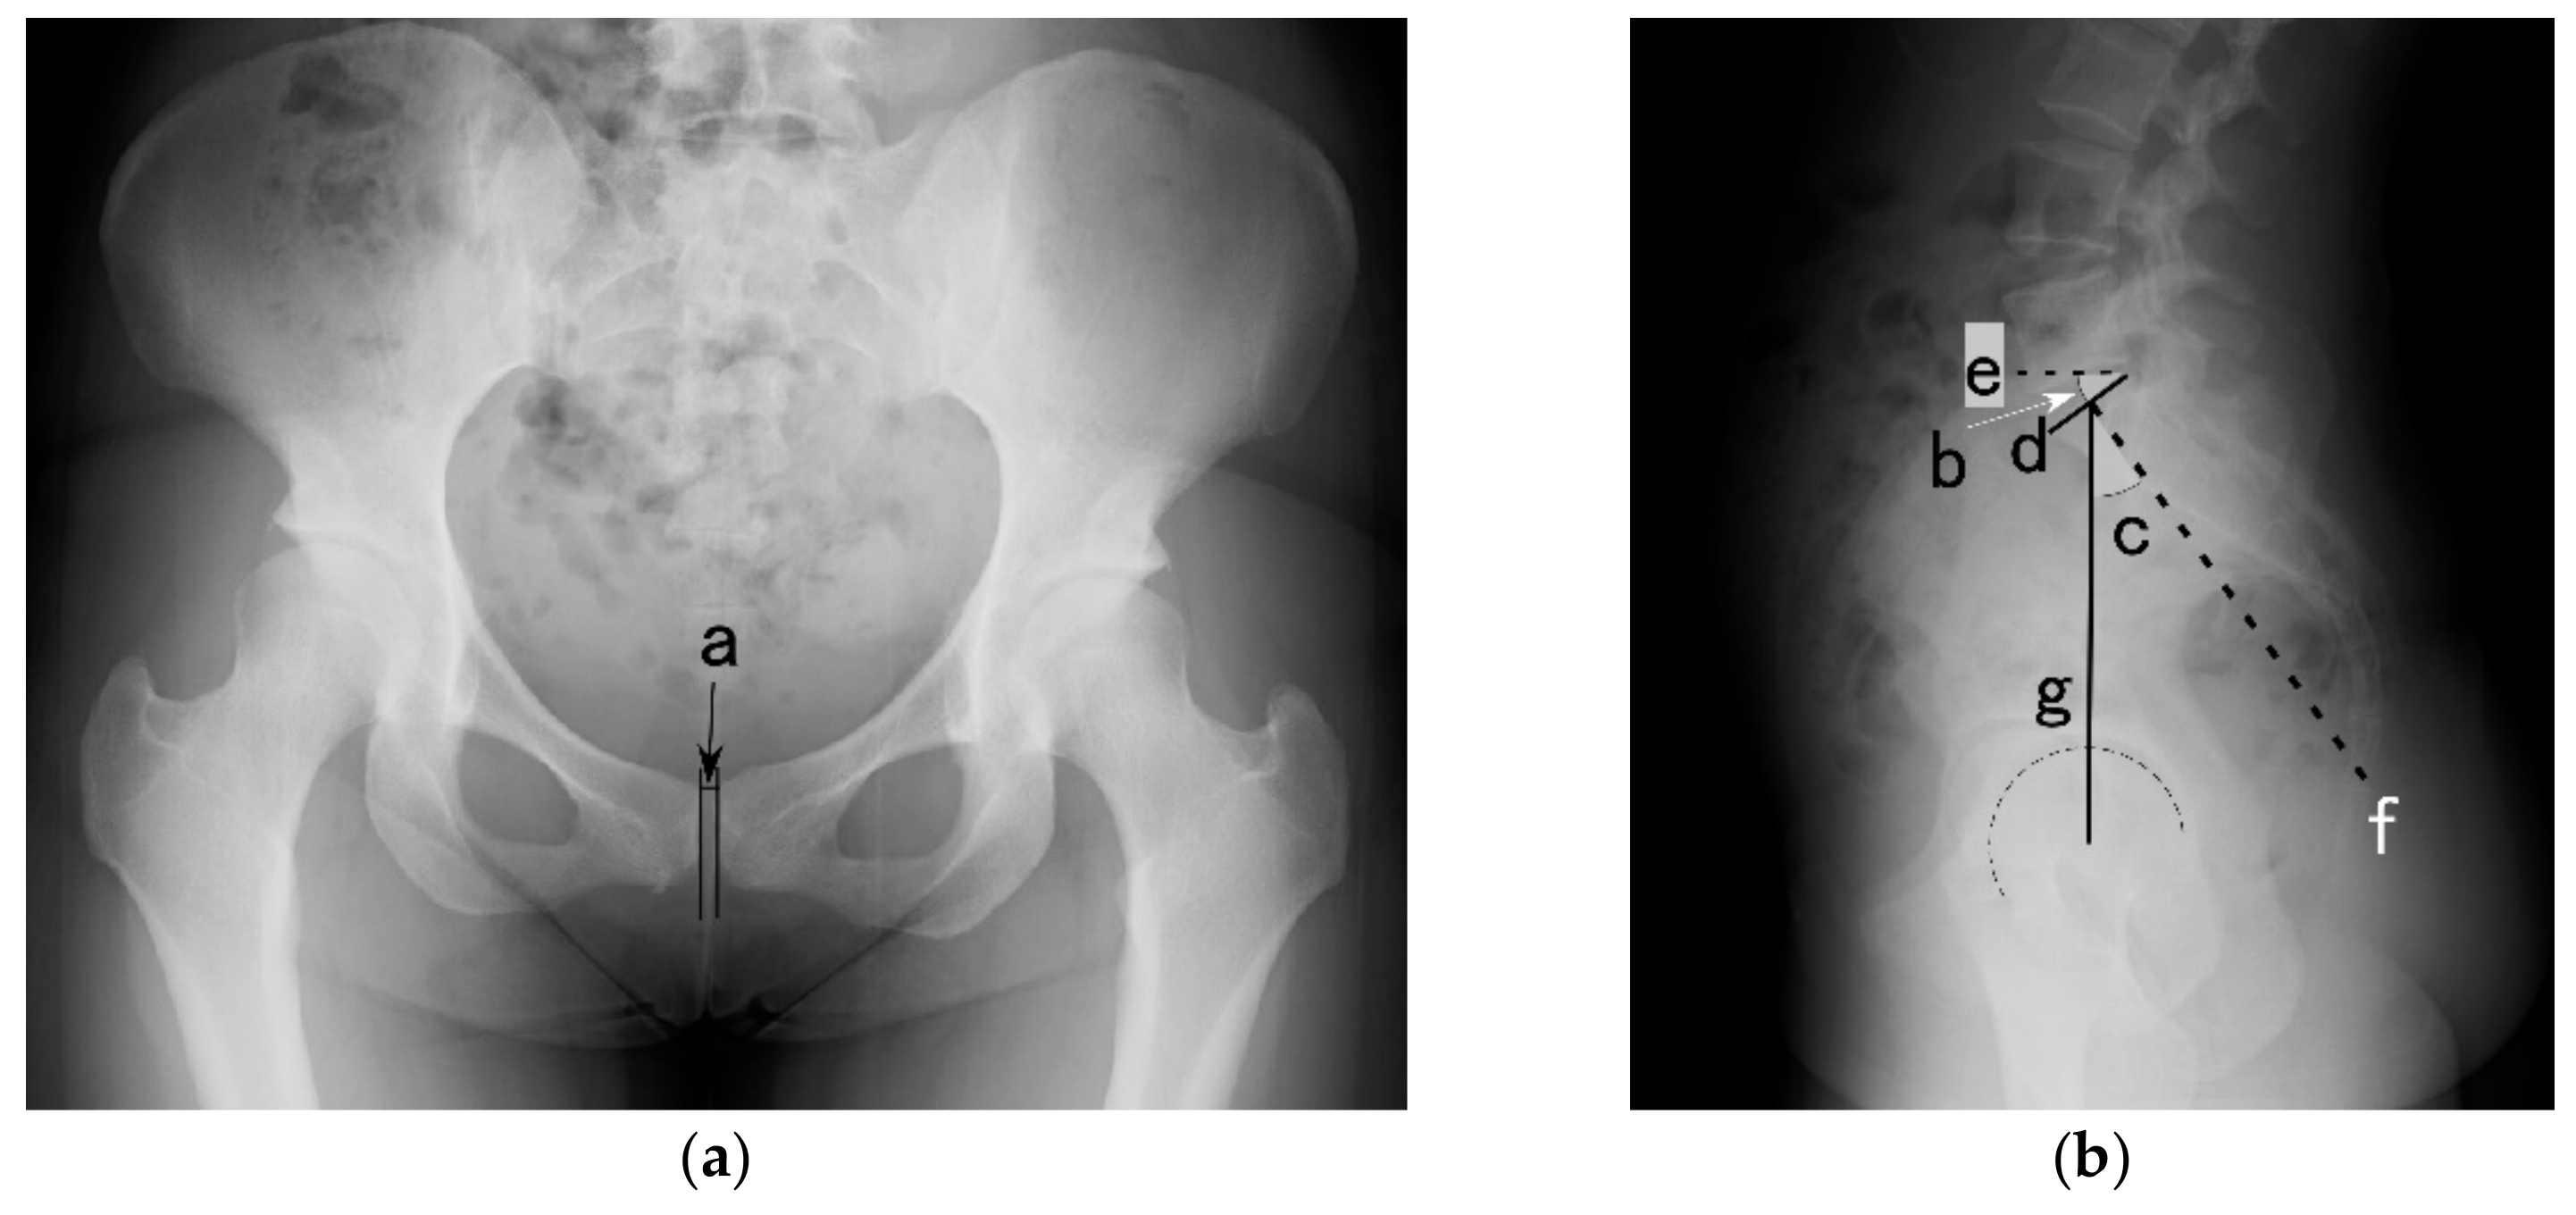

2.2. X-ray Assessment